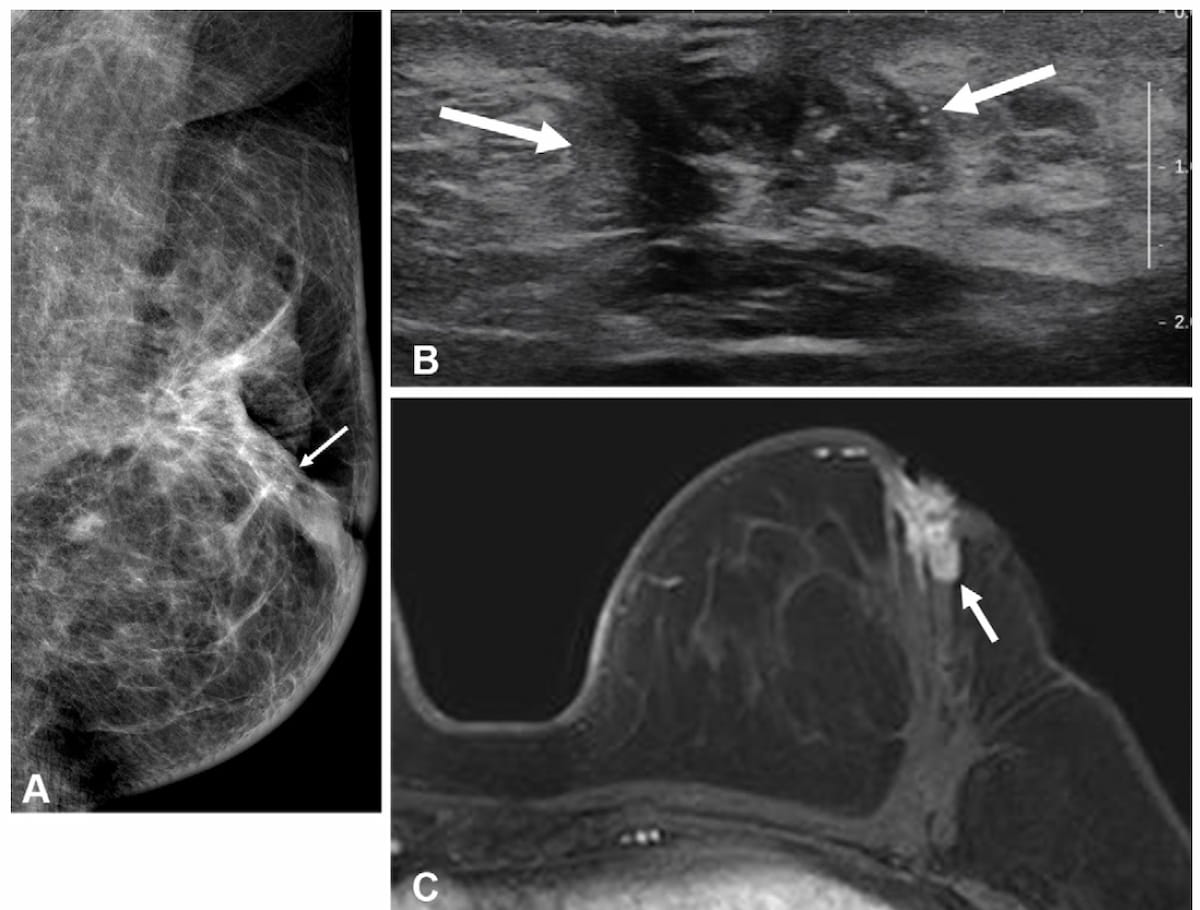

Here one can see mammogram, transverse ultrasound and T1-weighted MRI images for a 49-year-old woman who had a bloody nipple discharge two years after surgery for hormone receptor positive invasive breast cancer. The patient did not have a breast MRI prior to that surgery. The MRI above reveals an irregular, heterogeneously enhancing mass, which was subsequently confirmed as a recurrent invasive ductal carcinoma. (Images courtesy of Radiology.)